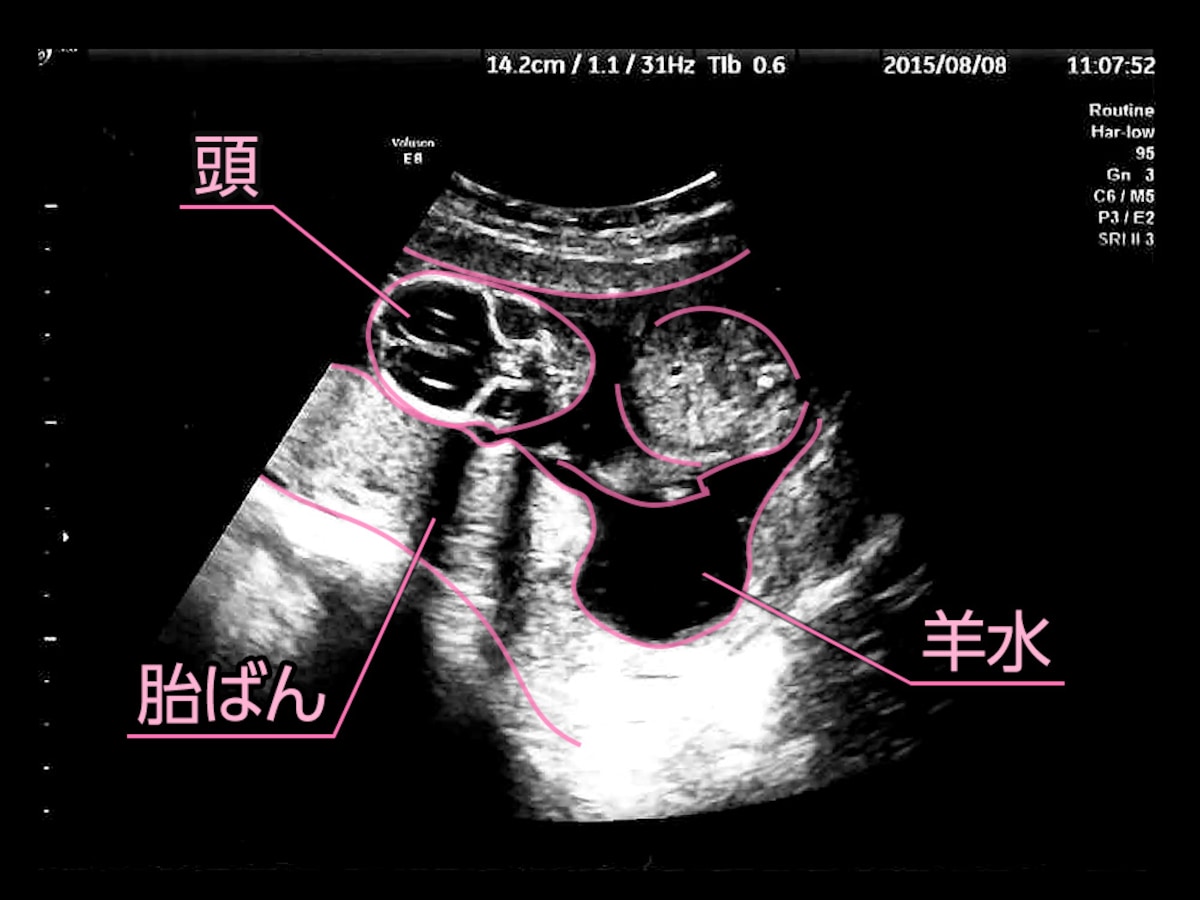

エコー写真を妊娠の経過別に紹介 見方や性別の見分け方

エコー写真を妊娠の経過別に紹介 見方や性別の見分け方

医療監修 エコー写真を妊娠の経過別に紹介 写真の見方や性別の見分け方 ママリ

エコー写真を妊娠の経過別に紹介 見方や性別の見分け方

エコー写真を妊娠の経過別に紹介 見方や性別の見分け方